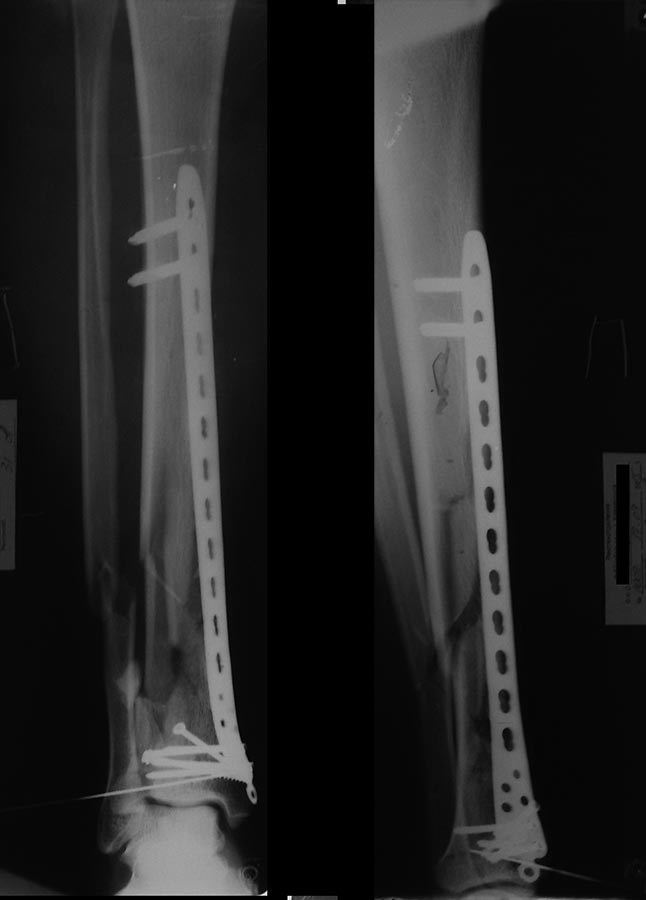

Уважаемый Кирилл предоставил отличный послеоперационный снимок. Мой

хуже, конечно. Но без ЭОП и через два разреза вышло вот так.

Там ещё вверху винт добавил и в эпифизе один спонгиозный с фиксацией

костного фрагмента и аутотрансплантата.